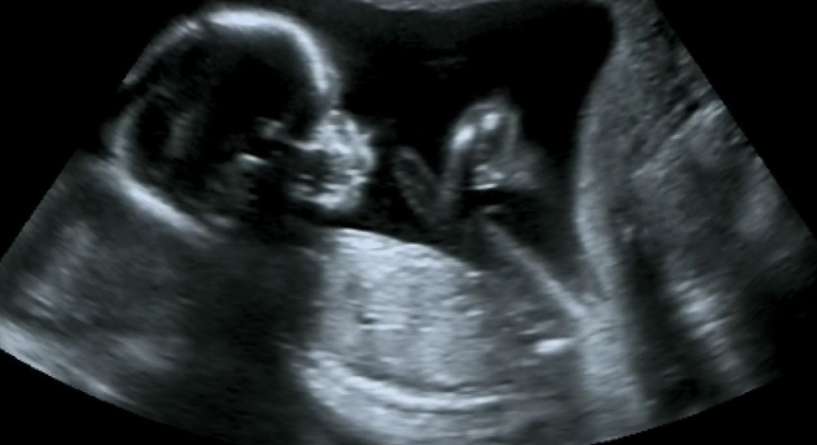

هل وصول المرأة للنشوة يؤثر على نوع الجنين من بين الاسئلة التي تطرحها النساء خلال الحمل بسبب شعورهن بالحيرة في حال تأثير الجماع على الجنين. اكتشفي ذلك الآن.

هل وصول المرأة للنشوة يؤثر على نوع الجنين

نسمع يومياً عن مختلف الطرق التي من شأنها أن تحدد نوع الجنين. أما بشأن هذا الموضوع، إذاً عليك أن تعلمي أنه يقال أن وصول المرأة النشوة خلال العلاقة الجنسية تزيد من نسبة الحمل بولد وذلك إذ إن النشوة تحفز حركة الكروموسوم y في الجسم. لذلك، إذا كنت ترغبين بالحمل بولد، عليك التأكد من وصول النشوة عند ممارسة العلاقة مع الزوج.

وإذا كنت تريدين الحمل ببنت، إذاً تأكدي من عدم وصول النشوة خلال العلاقة من أجل إضعاف نسبة الكروموسوم Y في الجسم.